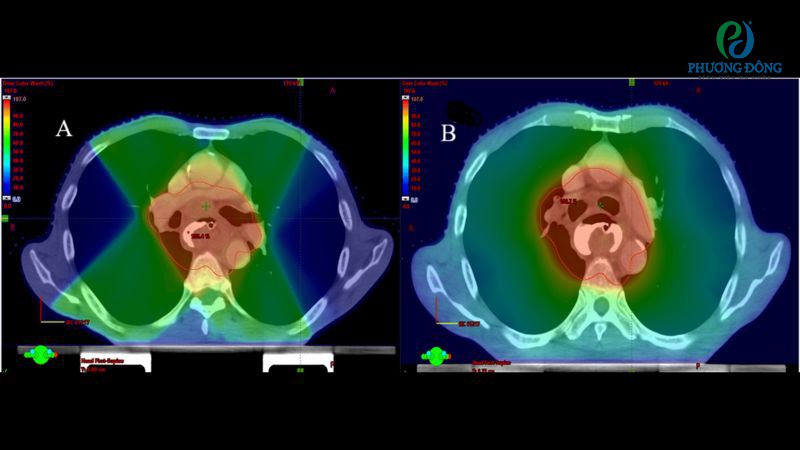

Chú thích: Phân bố liều dạng bản đồ màu trong khoảng từ 0% đến 107% đối với kế hoạch IMRT (A) và VMAT (B)

- A: Kế hoạch IMRT với nhiều chùm tia đồng phẳng được bố trí ở các góc quay (gantry) khác nhau.

- B: Kế hoạch VMAT thể hiện hai cung quay đối nghịch hoàn chỉnh với nhiều điểm điều khiển (177 điểm) nhằm tối ưu độ bao phủ khối đích.